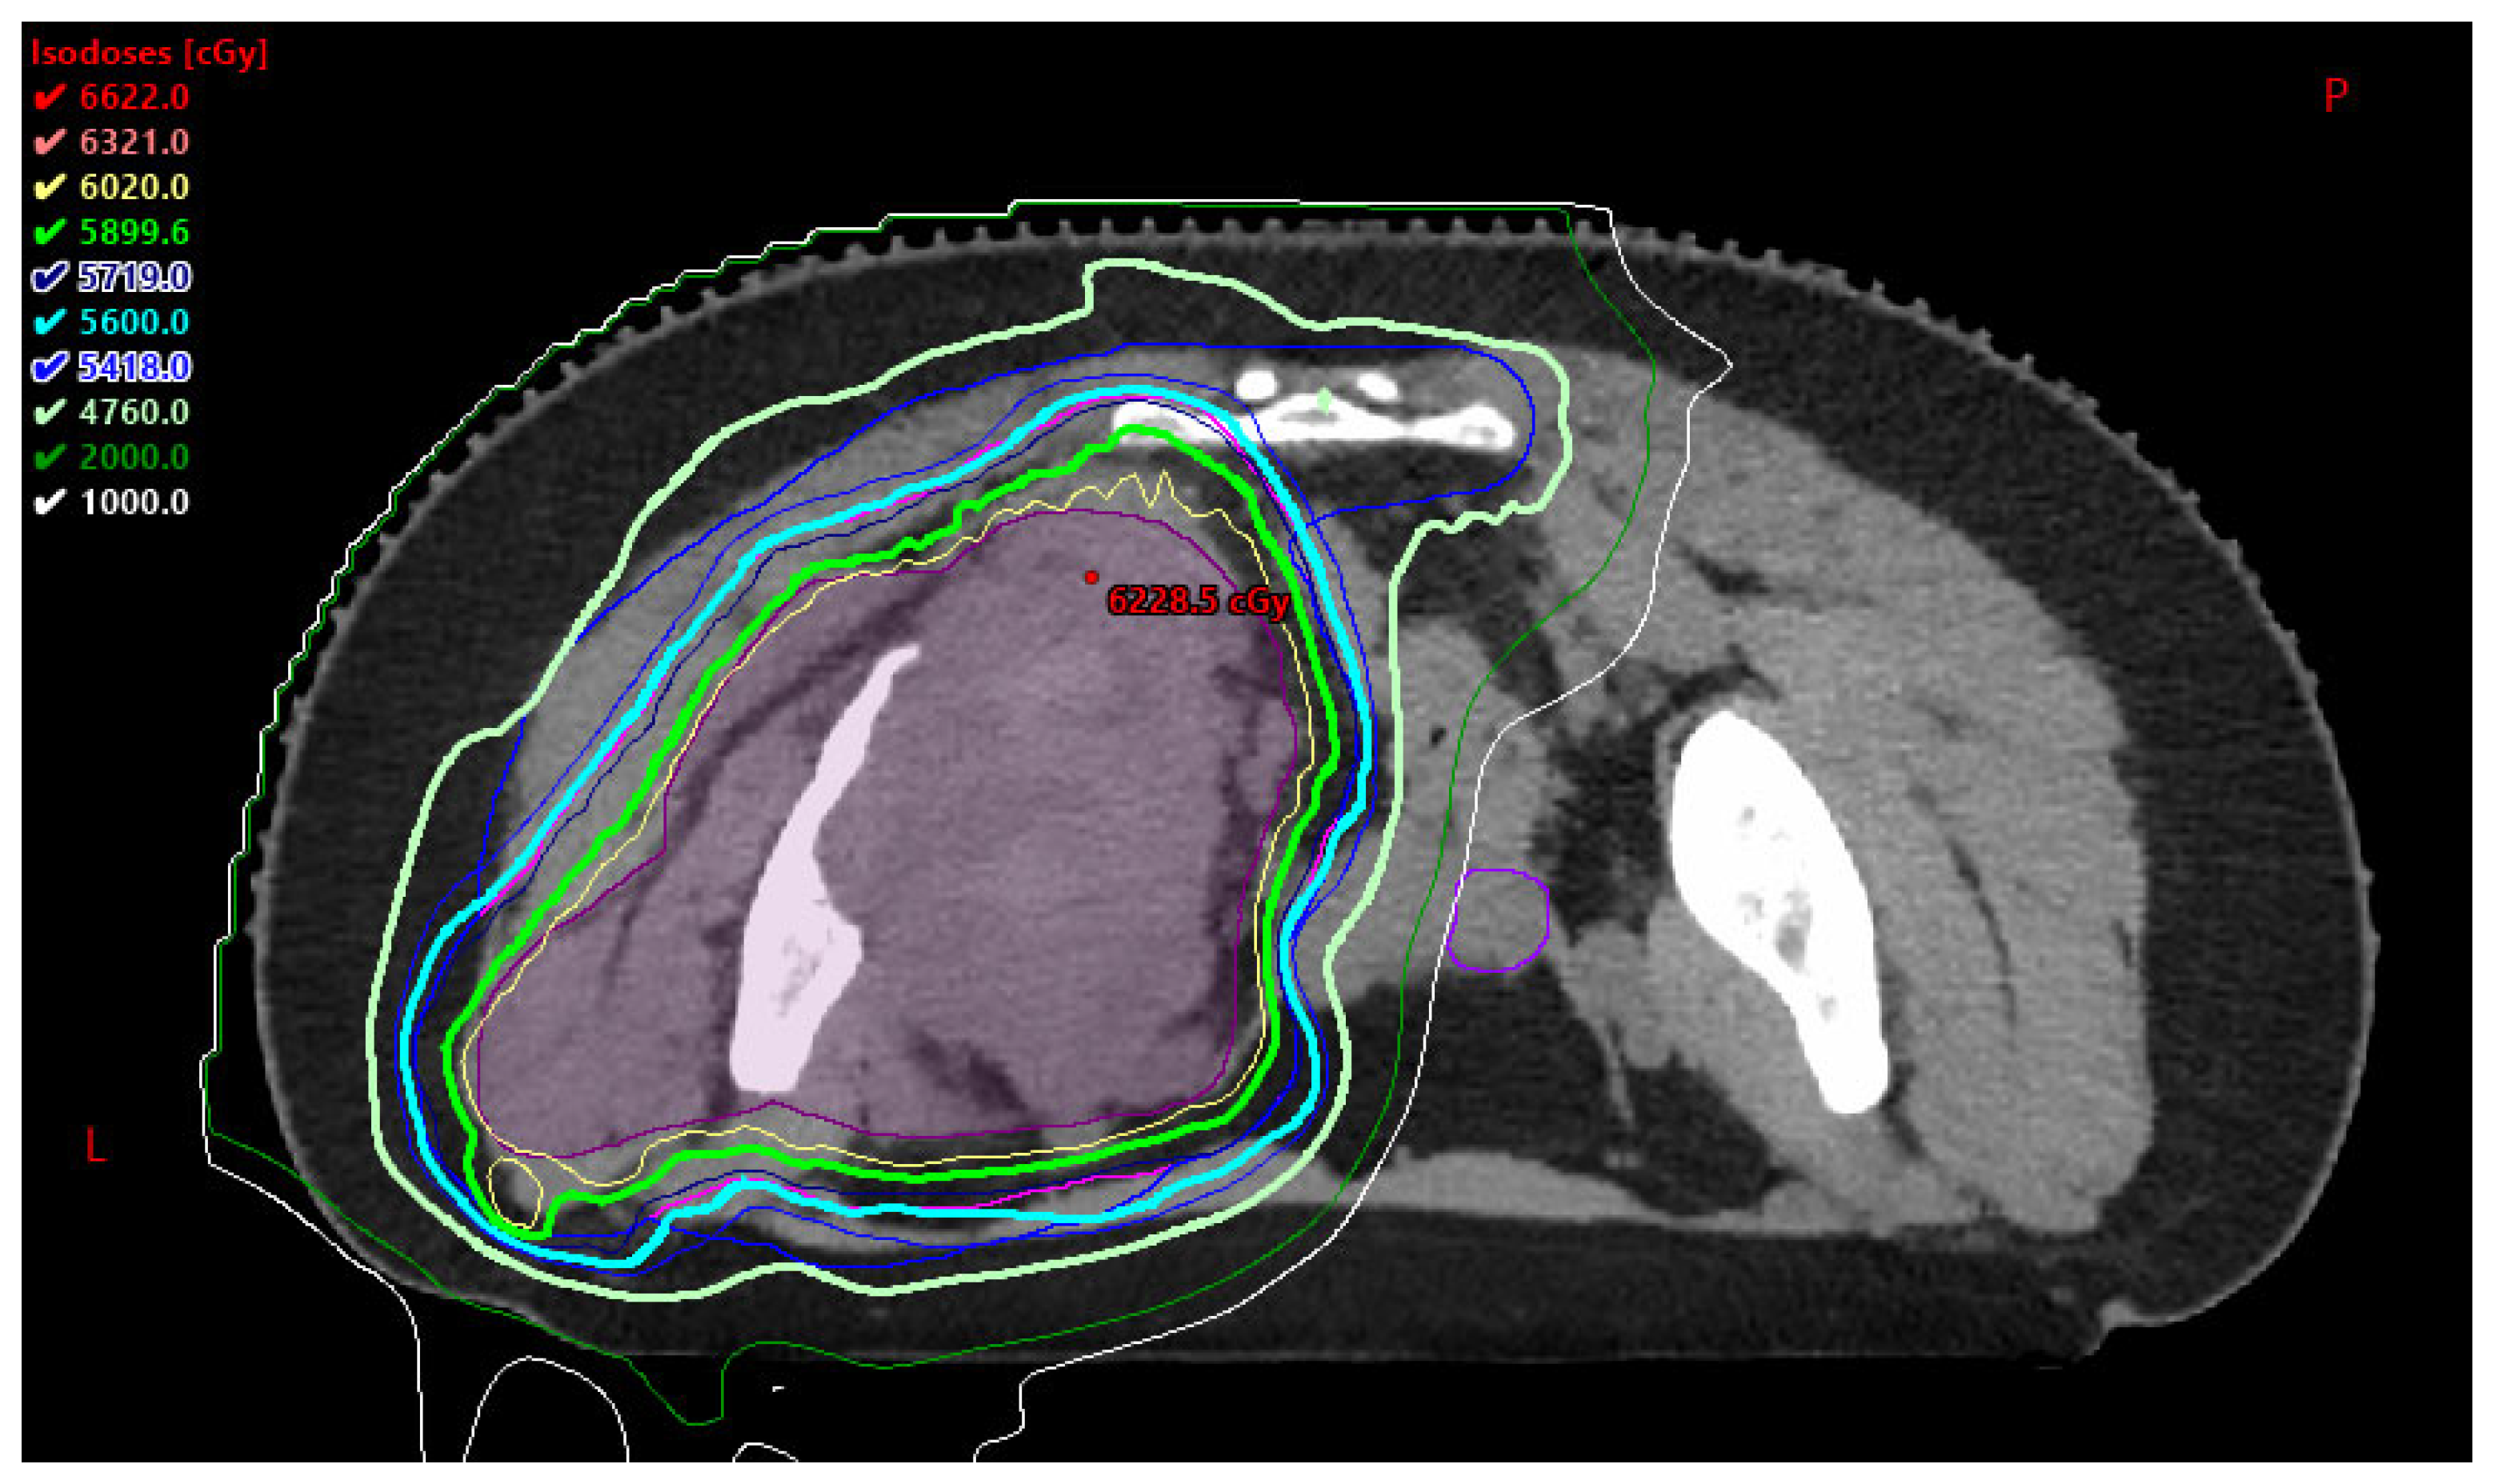

Figure 3. Representative axial image of a PBT plan for an AYA patient with unresectable pelvic Ewing sarcoma treated to 60.2 Gy in 28 fractions. PBT permitted a reduced dose to the contralateral ovary represented in purple. P: posterior L: left.

3.3.2. Fertility Risk and Preservation

It can be hypothesized that PBT may assist in reducing long-term fertility risks by minimizing the dose to genitourinary organs, the pelvis, and the hypothalamic-pituitary axis [14]. This is highlighted in Figure 3., which is an axial image of a PBT plan for an AYA patient with unresectable pelvic Ewing sarcoma treated to 60.2 Gy in 28 fractions. PBT permitted a reduced dose to the contralateral ovary represented in purple. An animal study was conducted in 2021 comparing anti-Müllerian hormone (AMH) levels (a biomarker of ovarian function) and primordial follicle survival after in vivo mouse pelvic gamma-ray radiation therapy (GRT) versus PBT [23]. Findings suggest that PBT can preserve ovarian function when ovaries are positioned distal to the spread-out Bragg peak (SOBP) in tumors of the abdominopelvic region [23], thereby demonstrating PBT as a superior modality for protection of fertility organs and encouraging future research on use of PBT in protection of fertility organs in women.